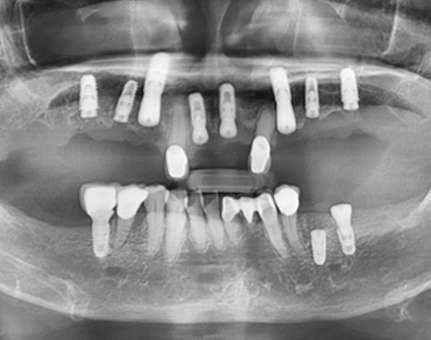

문치과 임플란트 사례

모든 전후 사진은 단순한 비교가 아닌,

환자분의 고민과 변화의 기록입니다.

문치과는 각자의 사연에 맞는 해답을 찾습니다.